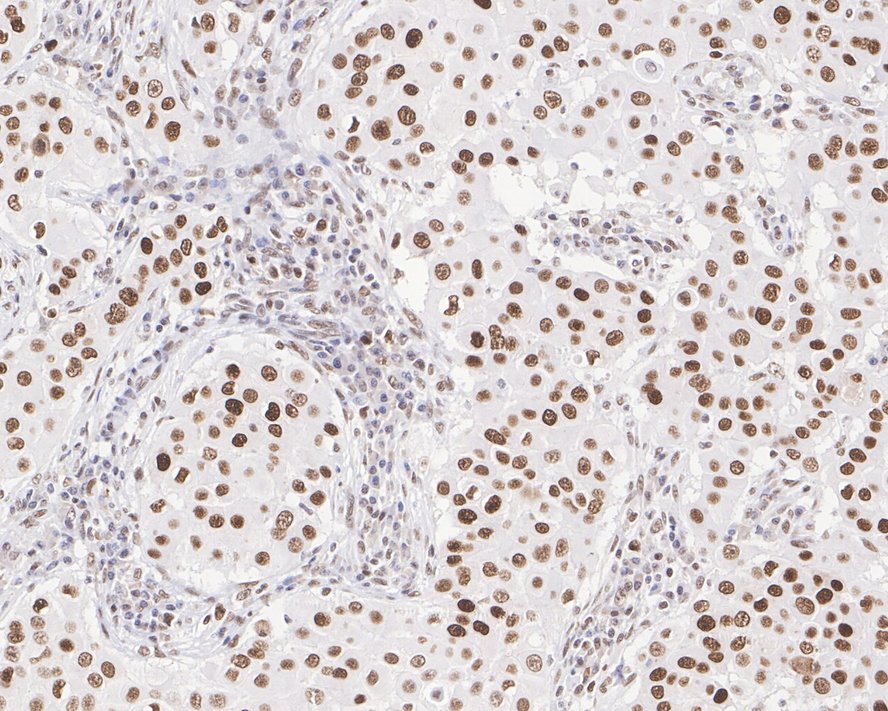

|   | Fig3:

Immunohistochemical analysis of paraffin-embedded human breast cancer tissue with Mouse anti-MSH2 antibody (EM1801-06) at 1/1,000 dilution. The section was pre-treated using heat mediated antigen retrieval with sodium citrate buffer (pH 6.0) for 2 minutes. The tissues were blocked in 1% BSA for 20 minutes at room temperature, washed with ddH2O and PBS, and then probed with the primary antibody (EM1801-06) at 1/1,000 dilution for 1 hour at room temperature. The detection was performed using an HRP conjugated compact polymer system. DAB was used as the chromogen. Tissues were counterstained with hematoxylin and mounted with DPX. |